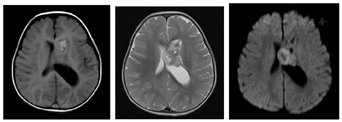

CT检查:左侧脑室体部团块状稍高密度影(图1),CT值约38 HU,大小约32.6 mm(前后径)×28.3 mm(左右径)×29.1 mm(上下径),左侧脑室后角明显扩大。MRI平扫+增强:(1)左侧脑室体部团块状混杂信号,T1WI、T2WI以等高信号为主,其内可见小片状低信号,FLAIR呈等高信号,DWI以高信号为主,增强扫描后肿块中心可见不均匀中等强化,余颅内未见明显异常强化(图2,图3,图4,图5);(2)MRS:肿块内测量NAA/Cr降低,Cho/Cr、Cho/NAA明显升高(图6);(3)头颅MRA未见明显异常;脑电图示轻度异常脑电图。影像检查提示高级别恶性肿瘤性病变,首先考虑间变性室管膜瘤,脉络丛乳头状癌及胚胎性肿瘤不除外。

GG在颅内的影像表现具有多样性,是一种少见的颅内原发性肿瘤,好发于大脑半球的浅表部位,多见于颞叶。影像上主要分为囊性、囊实性、实性3种。囊变和钙化被认为是节细胞胶质瘤的常见表现。Majores等[10]认为囊性病变并壁结节钙化是GG的特征性表现之一。本例发生于左侧脑室前角内,较为罕见,病变以软组织密度/信号为主,内见散在斑片状钙化,没有脑室外GG常见的囊变表现。病变局部与左侧脑室前角壁分界欠清,磁共振DWI呈较高信号,提示弥散受限,多考虑高级别肿瘤;结合MRS示NAA/Cr降低,Cho/Cr明显升高,术前影像首先考虑间变性室管膜瘤,其次考虑脉络丛乳头状癌。幕上室管膜瘤/间变性室管膜瘤分属WHO Ⅱ~Ⅲ级,幕上可位于侧脑室、脑实质或骑跨生长[11],肿瘤内可出现钙化、囊变和出血,密度或信号较为混杂,DWI提示弥散受限时,多考虑间变性室管膜瘤。本例未见明显囊变和出血成分,增强后未呈现室管膜瘤典型的环形强化[12],与室管膜瘤/间变性室管膜瘤不太符合。脉络丛乳头状瘤好发于脑室,尤其是侧脑室内,WHO分Ⅰ~Ⅲ级,Ⅲ级脉络丛乳头状癌具有高级别恶性肿瘤特征性表现:DWI弥散受限、合并出血、钙化、囊变,可突破侧脑室壁侵犯邻近脑实质,也可随脑脊液播散转移[13],因常起源于脉络丛,可分泌脑脊液,示侧脑室扩大,与本例较为相似。不过结合冠状位观察本例病变部分阻塞侧脑室侧孔可能是导致左侧脑室积水主要原因;因肿瘤生长挤压侧脑室壁变形扩大且分界不清,而并非直接侵犯侧脑室壁。此表现影像鉴别尤为重要,本例肿瘤DWI呈现较高信号,提示弥散受限,且MRS提示Cho/Cr明显升高,易与侧脑室好发恶性肿瘤混淆。术后回顾分析图像本例以实性为主伴少量钙化,不伴水肿及周围组织侵犯,发生于孟氏孔附近,符合节细胞胶质瘤良性表现,但考虑到弥散受限以及MRS中Cho/Cr明显升高,笔者认为不除外肿瘤向更高级别演变可能,这需结合临床长期随访,总结经验。